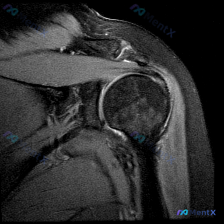

整理到一份肩关节影像病例资料,先放单张轴位T2加权MRI: > 影像基础:肩关节轴位T2加权序列,可见肱骨头、关节盂、肩胛下肌等结构,前下盂唇区域存在局灶性高信号影,肱骨头骨皮质完整,无明显关节积液或巨大占位。 想问问大家,仅根据这张图像的表现,第一反应会先往哪个方向考虑?有没有需要特别注意的鉴别点...

最近看到一份单一T1加权冠状位肩关节MRI影像,想评估是否存在盂唇病变。但了解到MRI诊断肩关节病变往往需要多序列联合判断,仅凭T1序列有一定局限性。大家怎么看这个影像的诊断价值?

整理了一个肩关节MRI轴位T1序列的病例资料,用户关心盂唇病变,但影像分析结果显示: - 盂唇形态完整,呈均匀低信号,未见明确撕裂征象 - 影像科指出单一T1序列对细微病变不敏感,建议补充PDFS序列、斜冠状位/斜矢状位 现在有几个问题想和大家讨论: 1. 单一轴位T1序列MRI对盂唇病变的评估局限...

看到一个肩关节病例,临床怀疑盂唇病变,但只提供了一张轴位T2加权MRI图像。先看影像分析结果: 轴位MRI表现: - 前、后盂唇形态基本完整,信号均匀,未见明确撕裂信号 - 肩胛下肌腱、冈下肌腱、肱二头肌长头腱信号正常,未见撕裂 - 肱骨头与关节盂对位良好,骨质及软组织未见明显异常 核心矛盾:临床怀...

最近看到一个肩部MRI病例,资料里只有T1序列冠状位影像。影像分析显示:肱骨头、肩胛盂形态正常,冈上肌腱走行连续无撕裂,上方盂唇呈三角形低信号、轮廓规则,未见明显的信号异常或撕裂征象。 虽然影像没找到盂唇的结构性病变,但患者很可能有持续性肩痛症状(不然也不会做MRI)。大家第一眼看到这种情况,会先往...